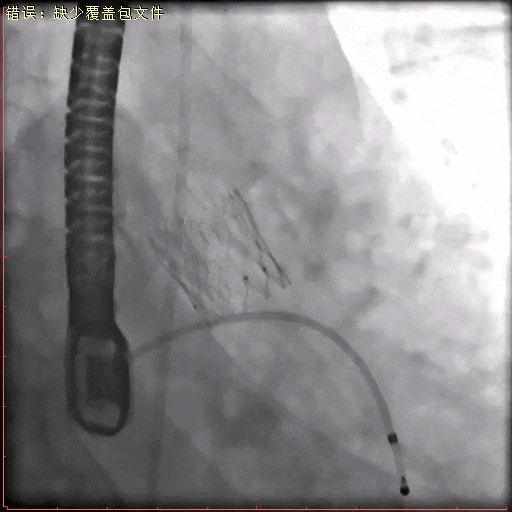

术中造影

瓣膜定位

瓣膜稳定释放至全展开位

脱钩后最终造影